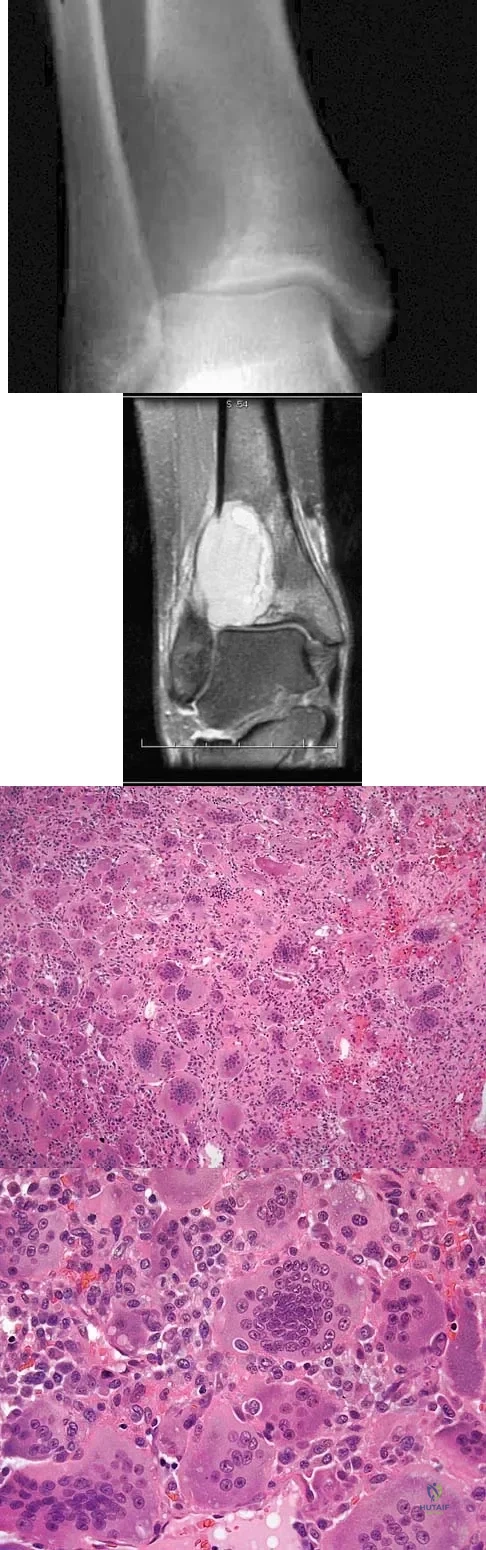

A 19-year-old girl has had pain and swelling in the right ankle for the past 4 months. She denies any history of trauma. Examination reveals a small soft-tissue mass over the anterior aspect of the ankle and slight pain with range of motion of the ankle joint. The examination is otherwise unremarkable. A radiograph and MRI scan are shown in Figures 45a and 45b, and biopsy specimens are shown in Figures 45c and 45d. What is the most likely diagnosis?

Explanation